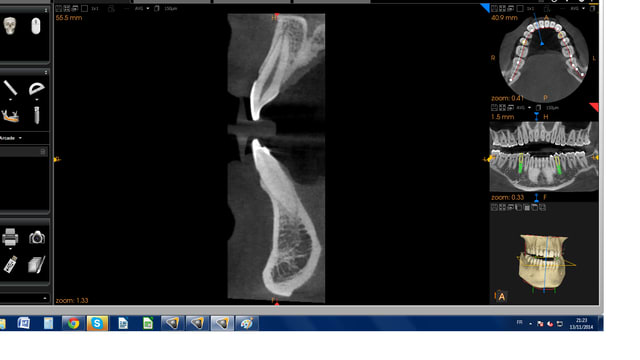

Cs3d zmn8hx - Eugenol

Cs3d2 ab0jys - Eugenol

Par contre en 3D je trouve que c'est la 8100 la meilleure. L'image est très fine, très nette et les artefacts sont assez discrets (on arrive à distinguer la vis dans l'implant ce qui est assez exceptionnel en 3D).